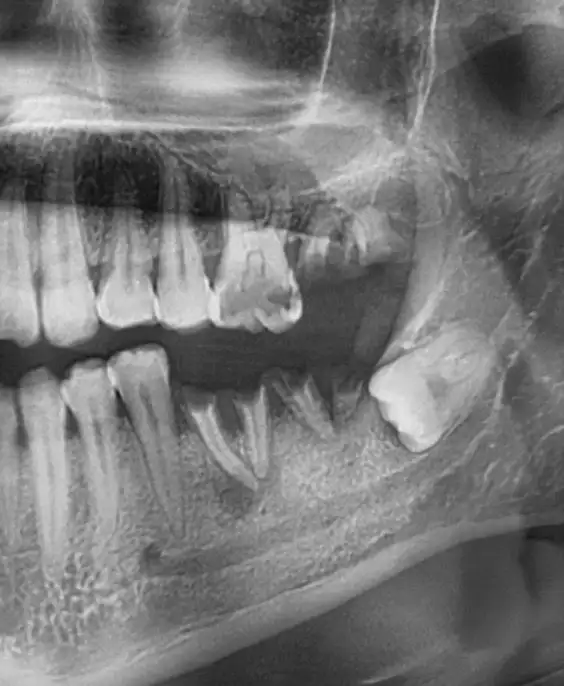

Подробный Обзор: Панорамный снимок зубов в Броварах